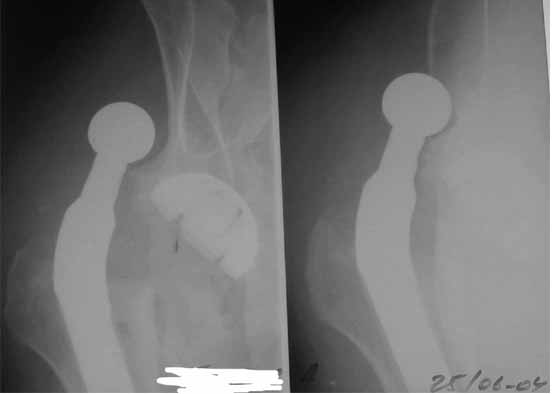

Во вложении - рентгенограммы после вывиха и после вправления.

Идея очень простая, в случае, если удасться прожить без вывиха 2.5-3 месяца, вероятность его возникновения в будущем значительно уменьшится. Оптимальный вариант - повторная иммобилизация на срок 6 недель с нагрузкой на ногу (как бы я ни не любил гипс, но этот путь проверенный и может дать результат). Если это невозможно, то исключительно осторожная реабилитация под строгим контролем без резких движений (спать в положении на спине с отведением и подушкой под коленкой и т.д.). Ходьба сама по себе не опасна, опасен переход от положения "лежа" в положение "полусидя" и "стоя" и наоборот.

Вывихи в раннем п/о периоде после протезирования (особенно через расширенные задне-боковые доступы) не так уж и редки. Если в данном случае вывих произошел в результате простого нарушения режима (поворот на бок), то ничего страшного нет. Больного нужно поднимать на ноги, но строго контролировать его движения. Если есть съемная отводящая шина - можно одевать ее для спокойствия.

Если же вывих произошел по причине неправильной ориентации ножки (чего по снимкам нельзя исключить), то конечно же он будет повторяться и

постельный режим тут ничем не поможет. Необходима ревизия с заменой неправильно имплантированного компонента и тщательным восстановлением капсулы и мышц в зоне сустава...